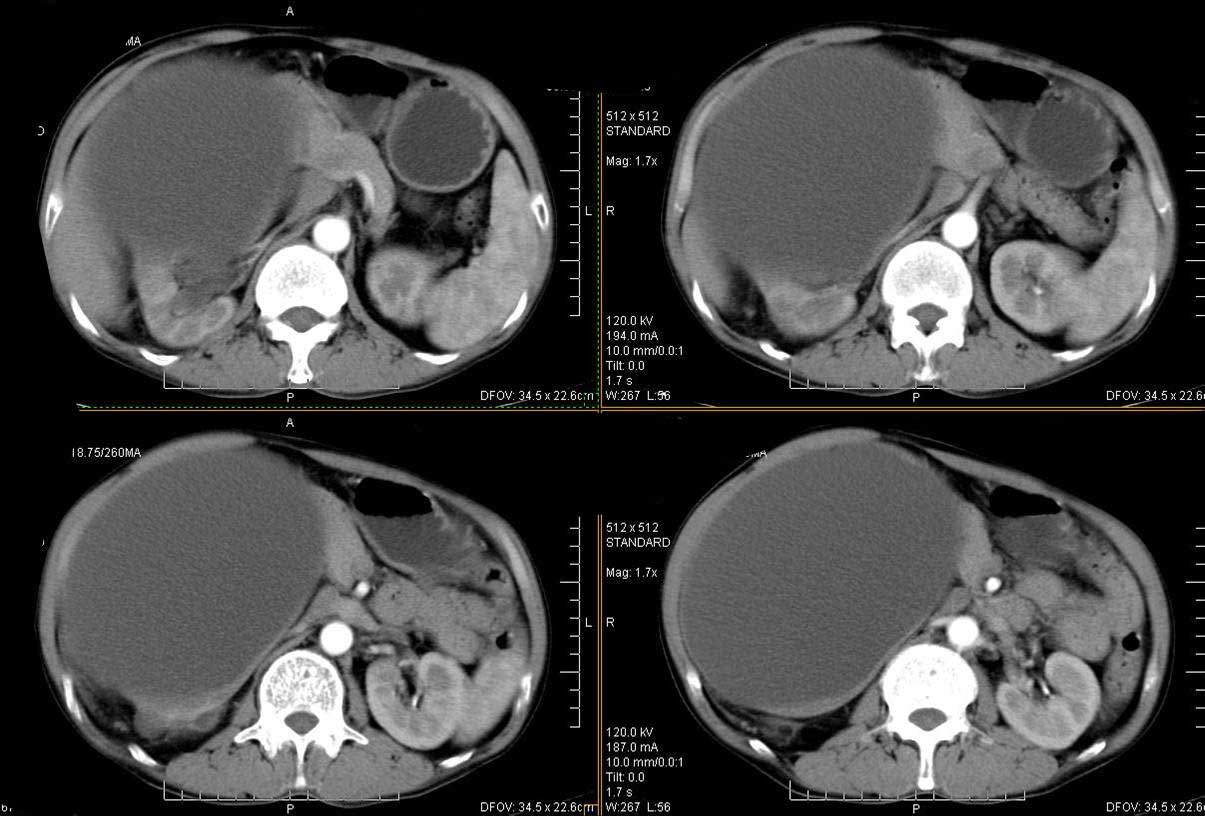

男性 60岁,腹部肿块4年余,肿块逐渐增大,活动性差,无血尿。

平扫

动脉期

门脉期

定位;肾明显与病灶杯口相交,可以肯定病变来自右肾。

定性;病灶囊性为主,前下部含实性成分,及钙化,部分壁厚薄不均。

肾囊实性病变有;1,囊性肾癌2,囊性肾瘤。3,复杂囊肿。4,重复肾伴积水。然2、3壁相对规则。

综上考虑;囊性肾癌》重复肾伴积水。